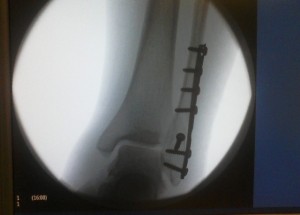

A few minutes later, I’m lying on the floor, my ankle swelling and feeling oddly separate from my leg. I’ll spare you the details (I wrote about it here, if you like that kind of thing), but I knew it was broken even though I was in serious denial. Around 2am, an x-ray technician confirmed my fears.

Hey girl, I got a similar injury in December - broke the ankle in 3 places and ended up with 11 screws and a plate at a Derby Lite class. (Scream Printer held my hand.) 4 months and 1 day after surgery, I skated for about an hour gently. I’m working back up to it. The tendonitis from not moving the ankle for 7-8 weeks really messed stuff up down there. I finished PT and I’m working carefully to get back up on skates.